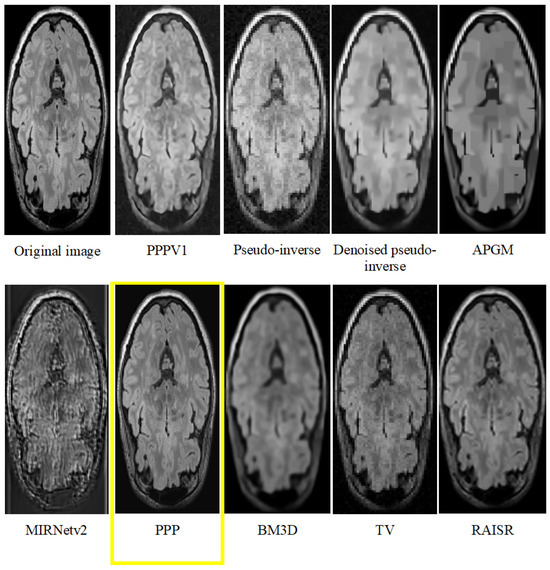

| Dataset 1 | Dataset 2 | |||

|---|---|---|---|---|

| Average | St.Dev | Average | St.Dev | |

| PPPV1 | 22.49 | 0.44 | 25.26 | 0.25 |

| Pseudo-inverse | 19.52 | 0.56 | 22.81 | 0.26 |

| Denoised pseudo-inverse | 20.36 | 0.51 | 23.73 | 0.28 |

| APGM | 19.91 | 0.34 | 23.78 | 0.22 |

| MIRNetv2 | 14.05 | 0.27 | 14.26 | 0.18 |

| PPP | 26.59 | 0.49 | 25.67 | 0.65 |

| BM3D | 20.58 | 0.82 | 23.72 | 0.36 |

| TV | 22.48 | 0.44 | 23.50 | 0.29 |

| RAISR | 21.99 | 0.43 | 25.77 | 0.32 |

| PPPV1 | 6.14 | 0.15 | 6.66 | 0.17 |

| PPP | 5.82 | 0.15 | 6.39 | 0.16 |

| Pseudo-inverse | 14.13 | 0.36 | 14.08 | 0.35 |

| Denoised pseudo-inverse | 14.13 | 0.36 | 14.08 | 0.35 |

| APGM | 13.86 | 0.35 | 13.03 | 0.33 |

| BM3D | 10.66 | 0.27 | 11.92 | 0.30 |

| TV | 12.22 | 0.31 | 12.82 | 0.32 |

| RAISR | 5.87 | 0.15 | 9.61 | 0.24 |

| MIRNetv2 | 7.18 | 0.18 | 7.95 | 0.20 |